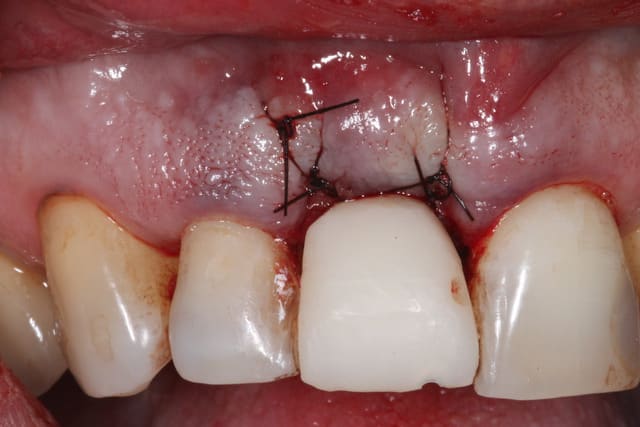

J'attendais d'avoir terminé le cas pour vous le présenter.

Il s'agit d'une EIIMCI avec comblement du gap.

J'ai utilisé un pilier plein que je n'ai pas déposé depuis la chirurgie.

Jour de la pose  7 mois  kkpghj - Eugenol